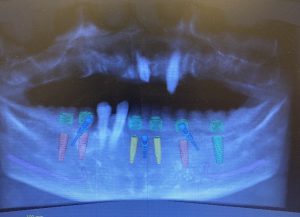

術前シュミレーション

サージカルガイトを用いたため術前シュミレーションと術後レントゲンを比較すると埋入角度、位置がほぼ一致しています。